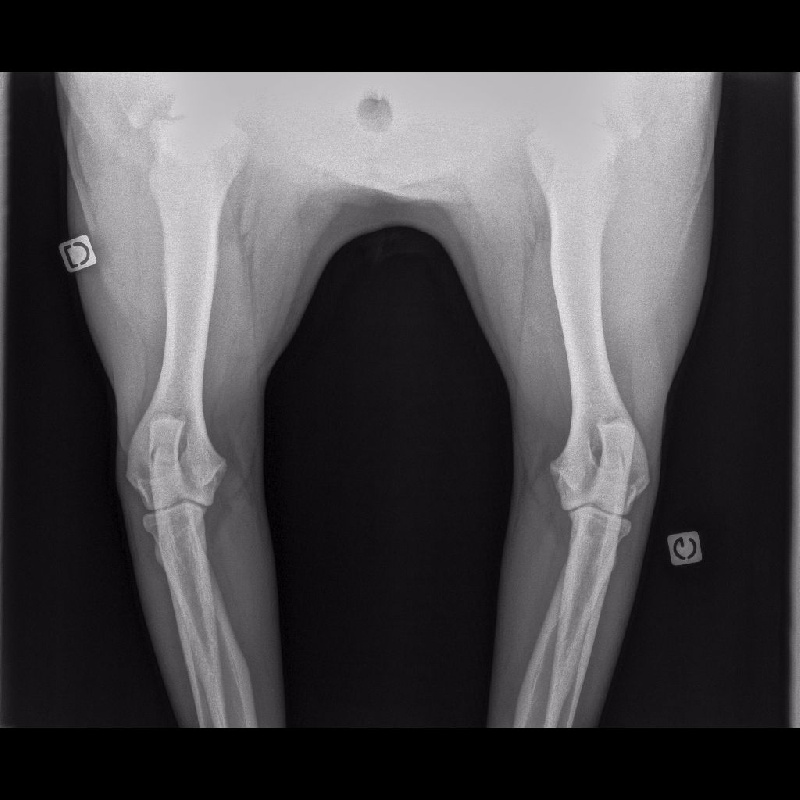

HANCHES